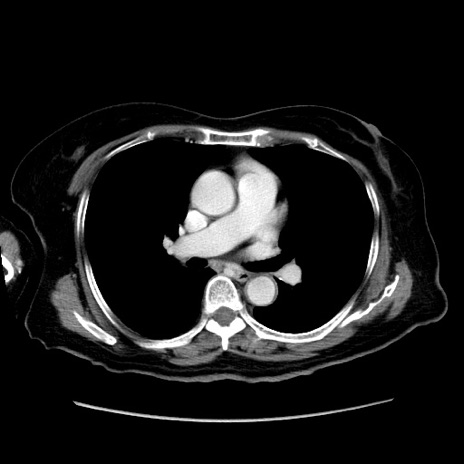

症例19(横断像)

【症例】80歳代女性

【主訴】下腹部痛

【現病歴】約8時間前より下腹部痛の出現あり、救急外来受診。

【既往歴】両側付属器切除

【身体所見】意識清明、下腹部正中に手術痕あり、その部位に一致して圧痛と反跳痛あり。腸蠕動音は亢進。

【データ】WBC 9300、CRP 0.15